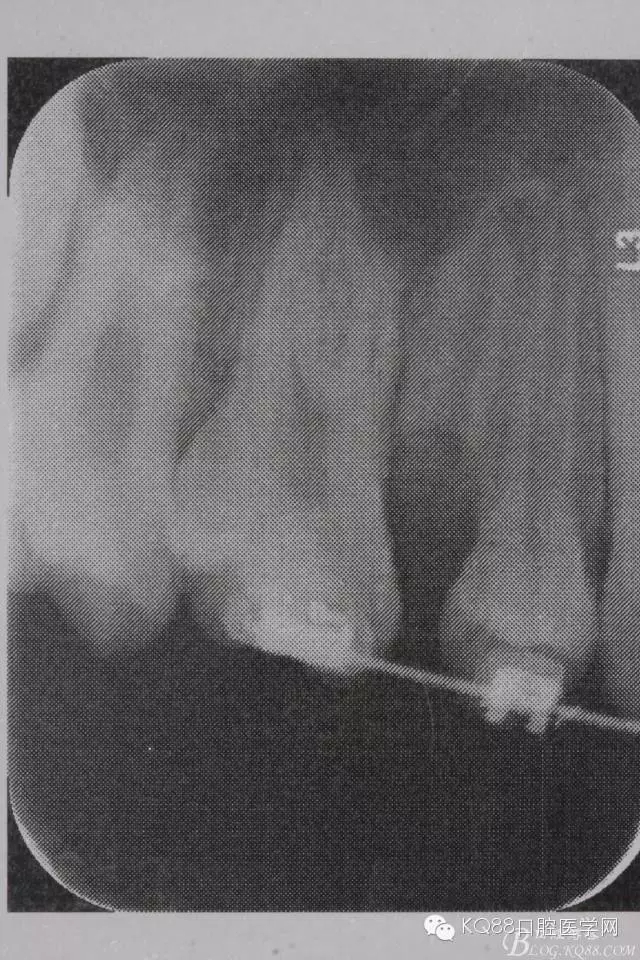

图4. 加拍局部根尖片,15牙根显露无疑,遂考虑拔除15,才能关闭16与14之间的间隙。